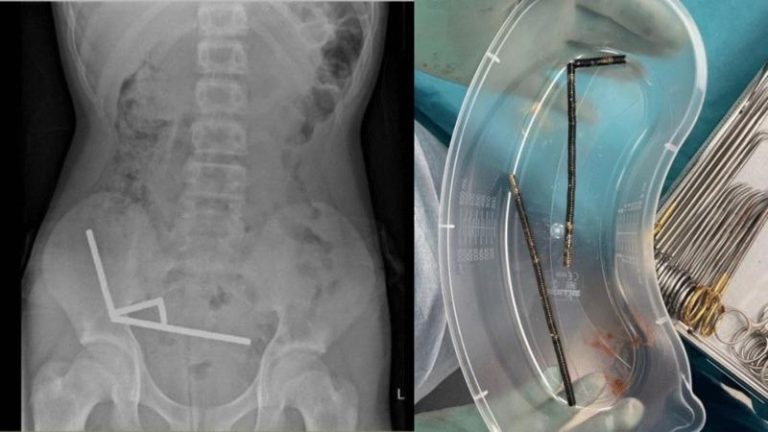

新西兰男童吞100磁铁引发剧烈腹痛,切除部分肠道后脱离险境。(取材自新西兰医学期刊)

新西兰医学期刊(New Zealand Medical Journal)日前刊登的一篇报告指出,一名13岁男孩吞下自己在中国电商平台Temu购买的多达100颗强力磁铁,腹痛难忍的他就医后,外科医生发现有组织坏死情形,不得不切除他的部分肠道。

澳洲卫报报导,这名青少年腹痛四天后被送往北岛陶朗加(Tauranga)的医院。医疗团队在报告中指出:「他透露,大约在一周前吞食约80到100颗5×2公厘大小的高功率钕(neodymium)磁铁」。

尽管新西兰早在2013年就禁止钕磁铁销售,但男孩仍通过在线购物平台Temu取得。X光显示,磁铁在男孩肠道排列成四条直线。报告指出:「这些磁铁位于肠道的不同部位,但因磁力作用而使各段肠道彼此沾黏。」

报告写到,磁铁的压迫造成男孩小肠与盲肠四个部位组织坏死,外科医师最终动手术切除坏死组织并取出磁铁。报告并未披露手术日期,男孩则在住院八天后出院返家。